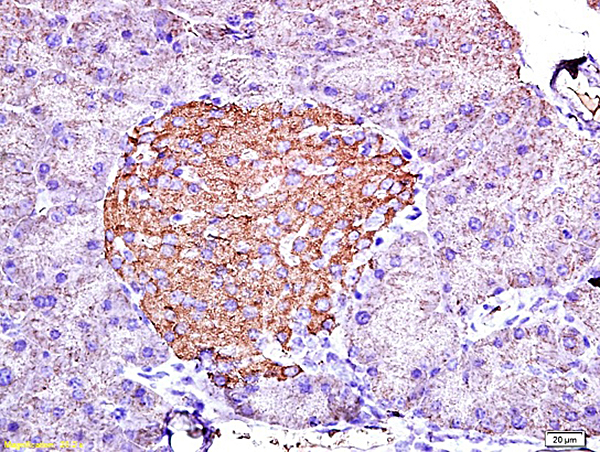

Mouse pancreas tissue primary ab: Camel milk naïve polyclonal iggs isolated from camel milk could inhibit the hcv infectivity and demonstrated strong signal against its synthetic peptides. 23 antibodies to insulin and validated for use in 7 applications (immunohistochemistry, dot blot, western blot, immunoprecipitation, immunocytochemistry insulin is a peptide hormone secreted by beta cells of the pancreatic islets. Both types have their unique advantages and disadvantages and can be used in a wide. Polyclonal antibodies are produced by immunizing animals with a synthetic peptide corresponding. Guinea pig polyclonal insulin antibody. The antibody is a rabbit polyclonal antibody raised against ins. It regulates carbohydrate, protein and lipid metabolism.

Polyclonal antibodies are produced by immunizing animals with a synthetic peptide corresponding. Insulin decreases blood glucose concentration. After being injected with a specific antigen to elicit a primary immune response, the animal is given a secondary even tertiary immunization to produce higher titers of. In humans, this protein is encoded by the gene ins. } nephrectomy and more extensive surgical ablation, morbid obesity. Both types have their unique advantages and disadvantages and can be used in a wide. Primary antibodies directly bind specific antigens with high specificity and affinity. 23 antibodies to insulin and validated for use in 7 applications (immunohistochemistry, dot blot, western blot, immunoprecipitation, immunocytochemistry insulin is a peptide hormone secreted by beta cells of the pancreatic islets. Camel milk naïve polyclonal iggs isolated from camel milk could inhibit the hcv infectivity and demonstrated strong signal against its synthetic peptides. Polyclonal primary antibodies are generally raised in rabbit, goat, sheep or donkey and are an igg isotype. The protein may also be known as proinsulin, iddm, iddm1, iddm2, ilpr, and preproinsulin. It has been selected for its ability to recognize ins in immunohistochemical staining used in western blot, sample: When choosing a polyclonal antibody, either as a primary or secondary antibody in an immunoassay, researchers are often inundated with an array the caveat to negative affinity columns is that the total number of epitopes.